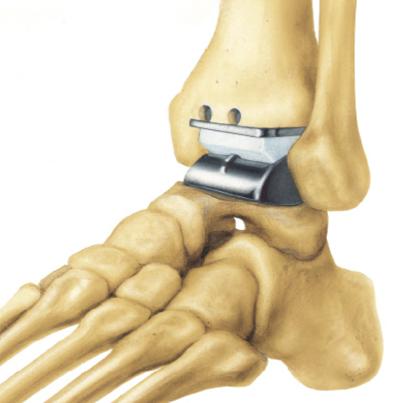

Αρθροπλαστική ποδοκνημικής

Πρόκειται για αντικατάσταση της φυσικής άρθρωσης με τεχνητή (μέταλλο και πλαστικό’). Η αρθροπλαστική έχει σκοπό να διατηρήσει κίνηση στην άρθρωση (τεχνητή πλέον). Αρθροπλαστικές ποδοκνημικής γίνονται από το 1970, όμως τα αρχικά αποτελέσματα ήταν απογοητευτικά. Τα εμφυτεύματα που χρησιμοποιούνται σήμερα έχουν γενικά βελτιωθεί, όπως και η γνώση και χειρουργική τεχνική, ιδιαίτερα σήμερα που υπάρχουν ορθοπαιδικοί χειρουργοί εξειδικευμένοι στις παθήσεις του ποδιού. Σε σχέση με τις αρθροπλαστικές γόνατος και ισχίου (που είναι οι πιο συχνές), οι αρθροπλαστικές ποδοκνημικής υστερούν τόσο σε ότι αφορά τις ενδείξεις (σε ποιον ασθενή πρέπει να γίνονται) όσο και στη ‘διάρκεια ζωής’ τους. Έχει ένδειξη για τελικού σταδίου αρθρίτιδα (όπως και η αρθρόδεση), όταν όλα τα άλλα μέτρα αποτυγχάνουν να ελέγξουν τον πόνο. Ιδιαίτερα ενδείκνυται σε ασθενείς που έχουν αρθρίτιδα και σε άλλες αρθρώσεις του ποδιού που απαιτούν αρθρόδεση. Η αρθροπλαστική μπορεί να διατηρήσει κάποιο εύρος κίνησης.

Η επέμβαση γίνεται με γενική ή ραχιαία αναισθησία. Γίνεται μια χειρουργική τομή 15 εκατοστών περίπου στην πρόσθια επιφάνεια της άρθρωσης. Τοποθετούνται εμφυτεύματα: μέταλλο στην κνήμη και τον αστράγαλο και ανάμεσά τους κινούμενο πολυαιθυλένιο (πλαστικό). Μετά το χειρουργείο χρησιμοποιείται γύψος για 3 εβδομάδες με ελάχιστη φόρτιση και κατόπιν αφαιρούμενος κηδεμόνας (μπότα) για άλλες 3 εβδομάδες επιτρέποντας τη φόρτιση.